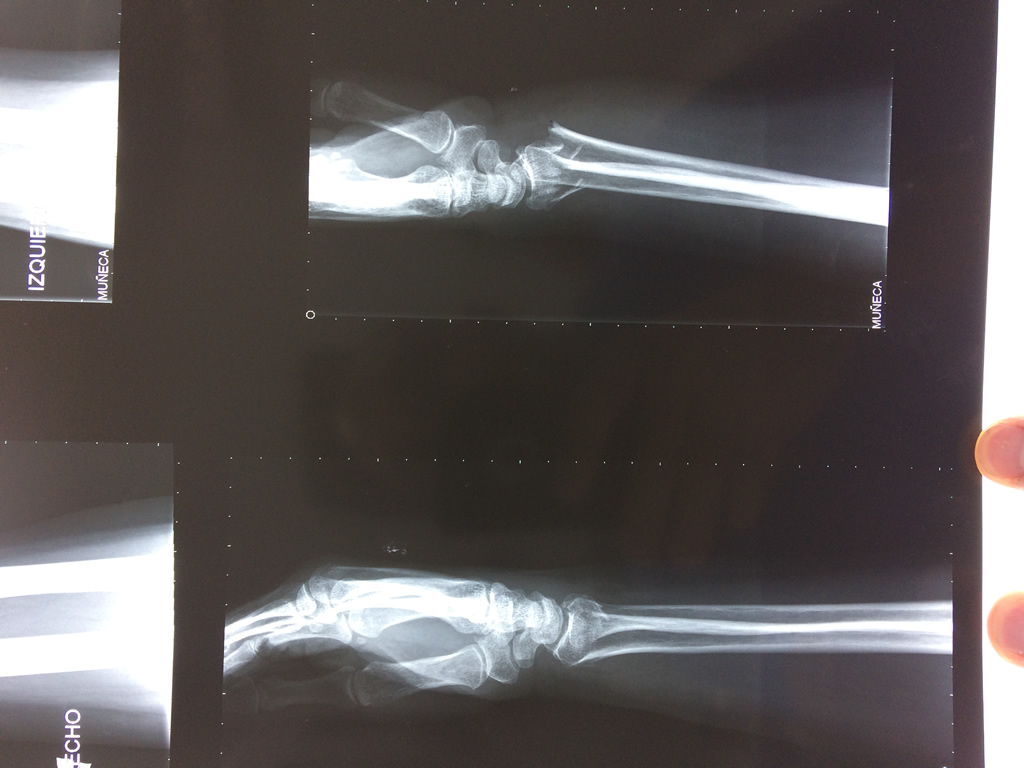

Cirugías de Húmero - Cirugías de Muñecas y Manos

Los procedimientos más comunes en cirugía de la mano son aquellos destinados a reparar traumatismos, incluyendo lesiones de tendones, nervios, vasos sanguíneos, y articulaciones; huesos fracturados; y quemaduras, cortes, y otros daños de la piel.